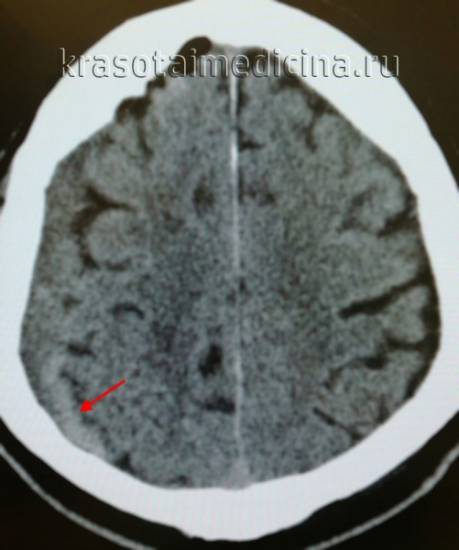

КТ-скан, демонстрирующий субдуральную гематому.

При любой травме головы необходимо получение медицинской помощи, включающей полное неврологическое обследование. В диагностике субдуральных гематом используются методы компьютерной и магнитно-резонансной томографии.

Решающими методами в диагностике субдуральной гематомы являются КТ и МРТ головного мозга. В диагностике острых гематом предпочтение отдается КТ головного мозга, которая в таких случаях выявляет однородную зону повышенной плотности, имеющую серповидную форму. С течением времени происходит разуплотнение гематомы и распад кровяных пигментов, в связи с чем через 1-6 нед. она перестает отличается по плотности от окружающих тканей. В подобной ситуации диагноз основывается на смещении латеральный отделов мозга в медиальном направлении и признаках сдавления бокового желудочка.

image

КТ головного мозга. Подострая субдуральная гематома справа